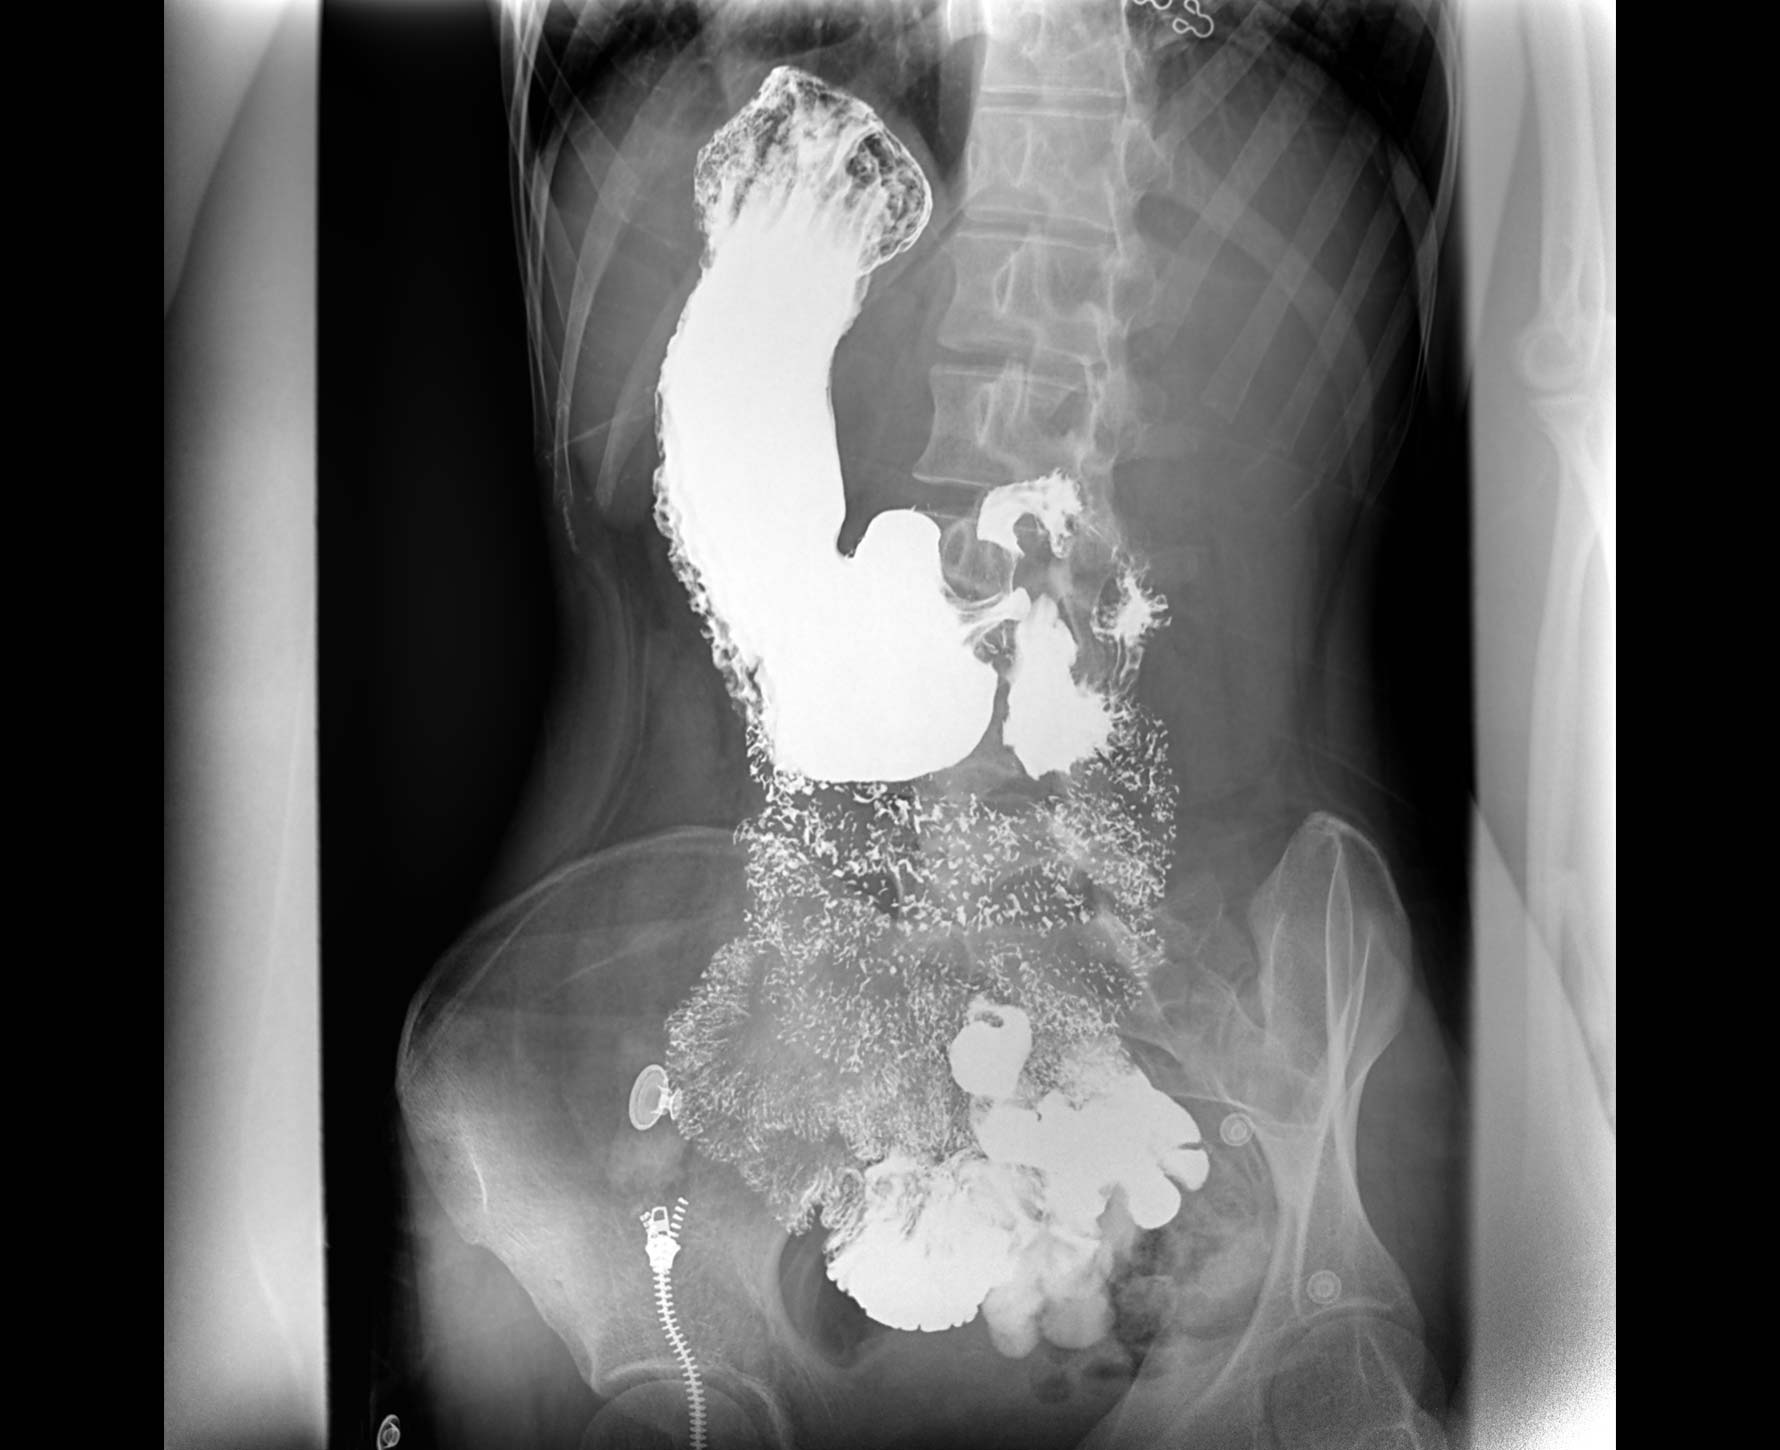

• 特有视频保存与回放功能

对胃肠造影检查影像实时保存,多次回放以便确定病灶部位,患者确诊好帮手,减少漏诊。

• 造影

适用于各种普通

及特殊胃肠造影检查